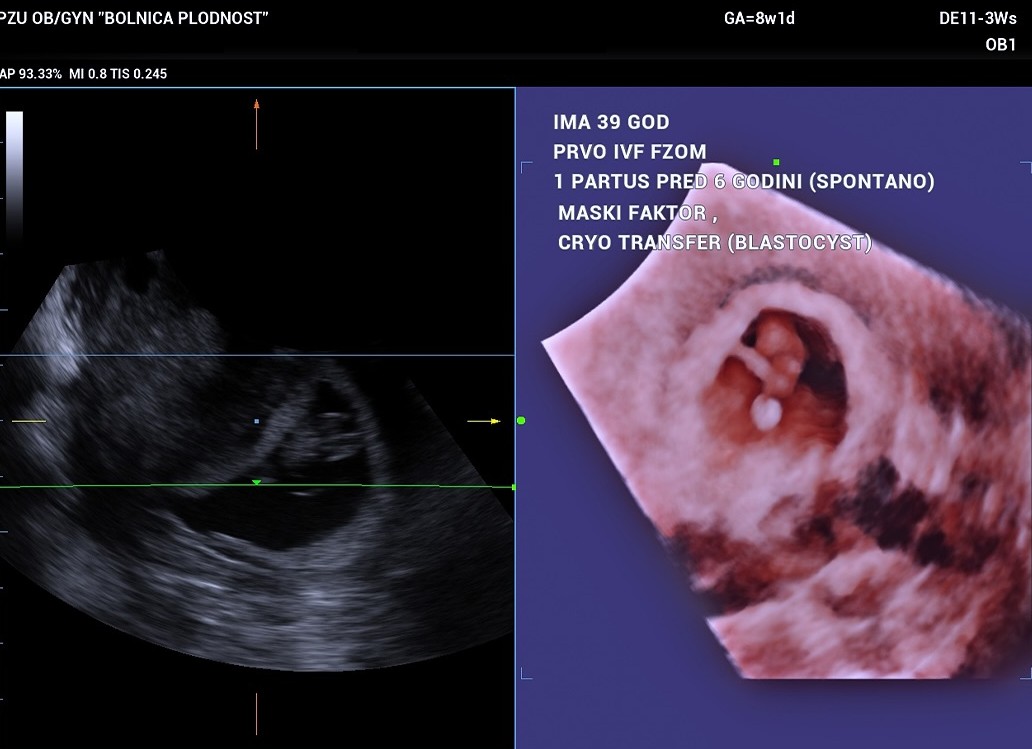

Case 1: 39-Year-Old Patient – Deferred Transfer and Frozen Blastocysts

A 39-year-old woman came to us six years after her last natural birth. During her first IVF procedure covered by the National Health Fund (FZOM), we noticed that her endometrium was not adequate on the planned day of embryo transfer. Rather than risking failure, we opted to freeze the embryos at the blastocyst stage and wait for a more optimal time. A few weeks later, the embryos were thawed and transferred successfully.

Result: Successful implantation and a healthy pregnancy – proof that careful assessment and patience deliver results.